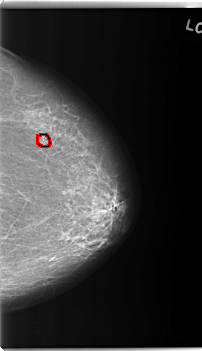

C_0231_1.RIGHT_CC

FILE: C_0231_1.RIGHT_CC.OVERLAY

TOTAL_ABNORMALITIES 1

ABNORMALITY 1

LESION_TYPE MASS SHAPE OVAL MARGINS ILL_DEFINED

ASSESSMENT 5

SUBTLETY 5

PATHOLOGY MALIGNANT

TOTAL_OUTLINES 1

BOUNDARY